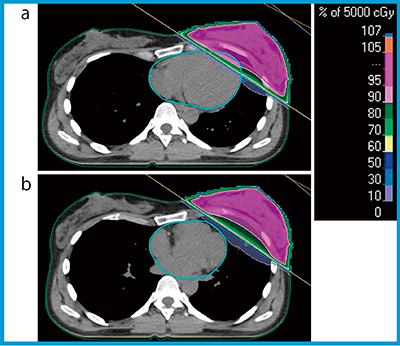

乳がん放射線治療においてDIBHは,深吸気息止め時の肺野の拡張を利用し,標的と心臓間のスペースを確保することで心臓線量を低減する目的で利用される(図1)。呼吸制御の手法は,スパイロメーターをベースとしたactive breathing coordinatorシステムなどで機械的に制御する手法(ABC-DIBH)と,患者の自発的(voluntary)な息止めによる手法(vDIBH)に大別3)される。また,呼吸停止位置の指標としては,皮膚マーキングと治療室レーザーを利用する簡便な方法,体表面に設置した各種サロゲートマーカー(指針,赤外線反射マーカーなど),あるいは光学的に体表面の三次元情報を取得する方法など,多様な選択肢が存在する。さらに,得られた呼吸制御に関する情報を患者に音声や視覚情報でフィードバック(visual feedback:VFB)し,その再現性やスループットを向上させる試み4)も行われている。

図1 全乳房照射における自由呼吸時(a)と深吸気息止め時(b)の

線量分布の比較